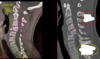

72

¿Qué fractura es esta?

Fractura por estallido